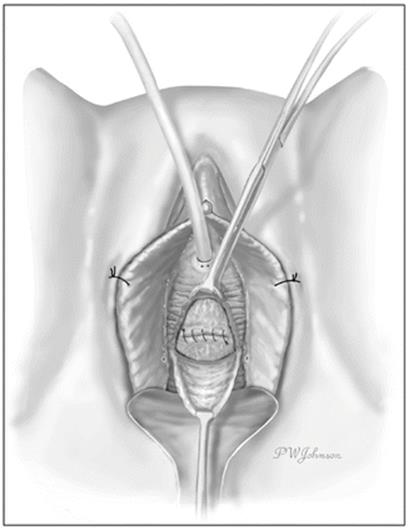

The periurethral fascial flaps are reapproximated with interrupted 3.0 synthetic absorbable suture in a perpendicular orientation to the urethral closure line to minimize overlap and the risk of postoperative urethrovaginal fistula formation (Fig. 11.11). Care is taken to secure the periurethral fascial flaps in order to close all the dead space.

Fig. 11.11

The periurethral fascia is closed with care to obliterate any dead space (Used with permission from Rovner ES. Urethral diverticula. In: Female Urology, 3rd ed. Edited by Raz S, Rodriguez LV. Philadelphia: Saunders Elsevier; 2008)